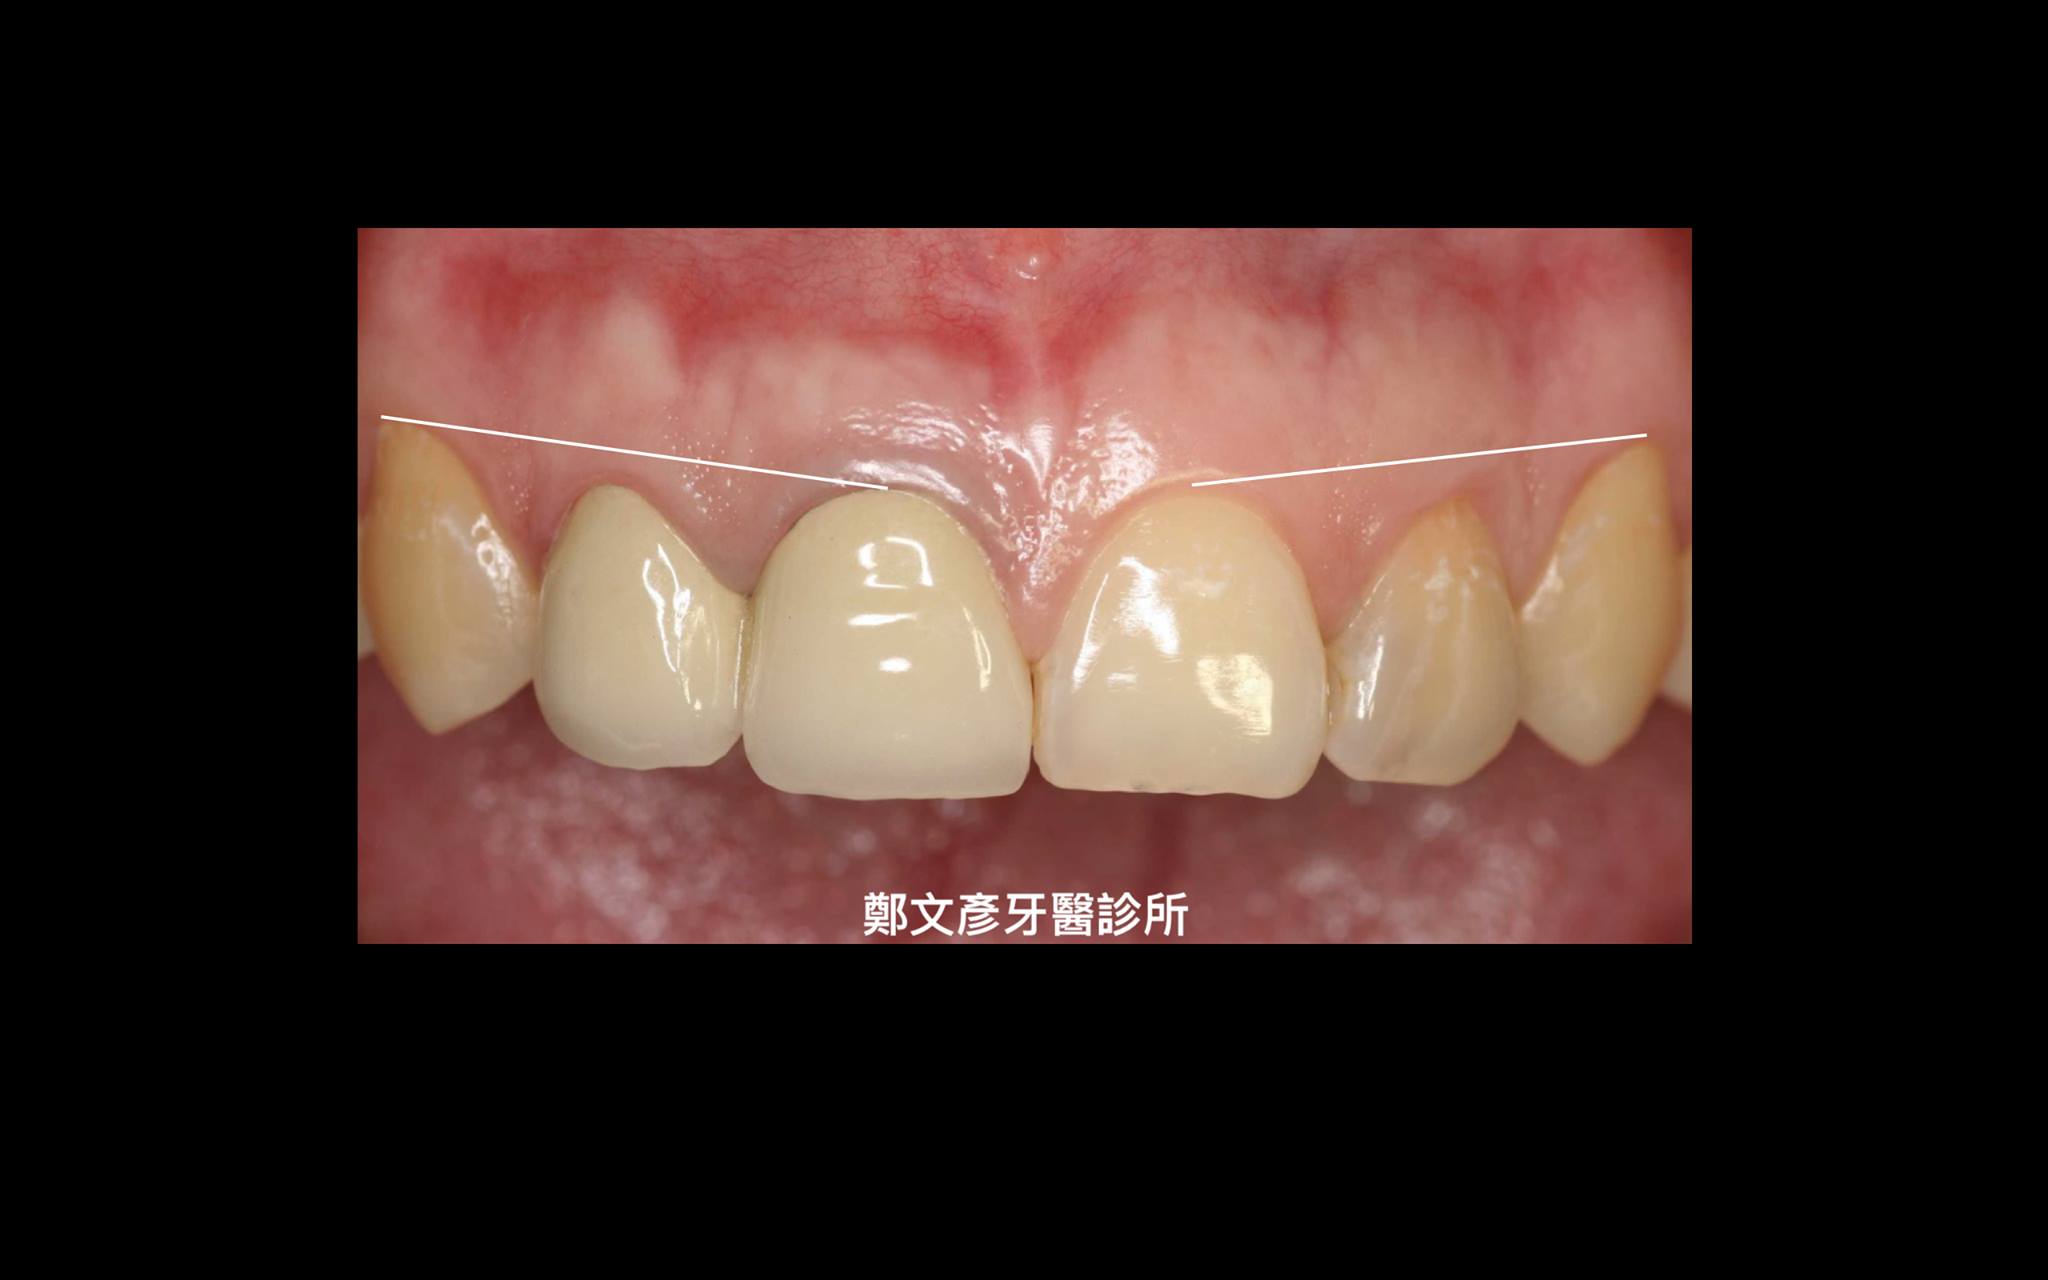

前牙植牙美學及軟組織轉移

植牙美學